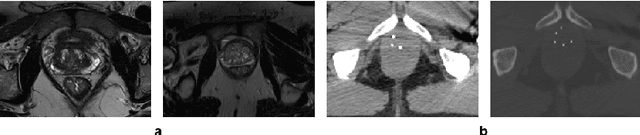

Abstract:Deep learning has shown unprecedented success in a variety of applications, such as computer vision and medical image analysis. However, there is still potential to improve segmentation in multimodal images by embedding prior knowledge via learning-based shape modeling and registration to learn the modality invariant anatomical structure of organs. For example, in radiotherapy automatic prostate segmentation is essential in prostate cancer diagnosis, therapy, and post-therapy assessment from T2-weighted MR or CT images. In this paper, we present a fully automatic deep generative model-driven multimodal prostate segmentation method using convolutional neural network (DGMNet). The novelty of our method comes with its embedded generative neural network for learning-based shape modeling and its ability to adapt for different imaging modalities via learning-based registration. The proposed method includes a multi-task learning framework that combines a convolutional feature extraction and an embedded regression and classification based shape modeling. This enables the network to predict the deformable shape of an organ. We show that generative neural networkbased shape modeling trained on a reliable contrast imaging modality (such as MRI) can be directly applied to low contrast imaging modality (such as CT) to achieve accurate prostate segmentation. The method was evaluated on MRI and CT datasets acquired from different clinical centers with large variations in contrast and scanning protocols. Experimental results reveal that our method can be used to automatically and accurately segment the prostate gland in different imaging modalities.